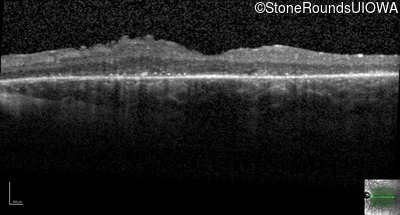

| Age at visit: 21 years |